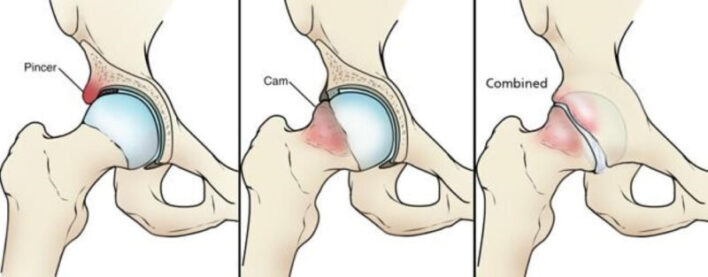

Có ba loại FAI: gọng kìm (pincer), chỏm (cam) và hỗn hợp (mixed). FAI loại gọng kìm là do ổ cối che phủ chỏm xương đùi quá mức, trong khi FAI loại chỏm là do giảm khoảng cách rìa xiên giữa cổ – chỏm xương đùi. FAI loại gọng kìm thường xảy ra ở phụ nữ trung niên, trong khi FAI loại chỏm phổ biến hơn ở nam giới ở độ tuổi tứ tuần. Phần lớn các trường hợp FAI có các đặc điểm của cả loại gọng kìm và chỏm.

Trong khi rách sụn viền liên quan đến cả hai loại FAI có xu hướng xảy ra ở vùng trước trên, thì những bất thường về xương ở FAI loại chỏm (cam) và gọng kìm gây ra các kiểu rách sụn viền khác nhau.

- Trong kiểu chạm gọng kìm, sự tiếp xúc lặp lại giữa cổ xương đùi và mặt trước nhô ra của vành ổ cối dẫn đến thoái hóa, rách sụn viền, hình thành các hạch ở bên trong sụn, và đôi khi là cốt hoá sụn viền.

- Trong va chạm kiểu chỏm, sự tiếp xúc bất thường giữa điểm nối cổ – chỏm xương đùi và ổ cối tạo ra sự mài mòn từ trong ra ngoài của sụn ổ cối và sự tách lớp giữa sụn ổ cối với sụn viền và xương dưới sụn liền kề. Rách sụn viền có xu hướng xảy ra trên bề mặt khớp hơn là bề mặt bao khớp.